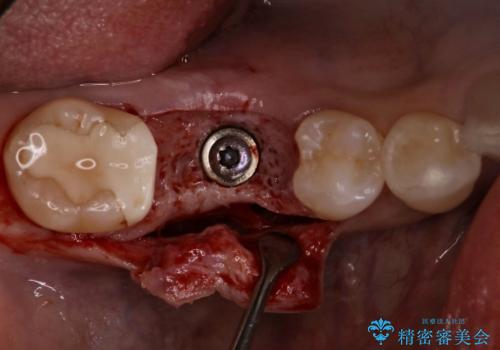

- 他院で抜歯されて、今後どうしたらいいのかを相談された患者様です。

抜歯を行った後は、Br、義歯、インプラント、何もしないという選択肢のメリットデメリットを説明させていただき患者様がインプラント治療を希望されたので今回治療させていただくことになりました。

二回の手術を終えて最終的な被せ物が入るまで6〜8ヶ月かかると思います。

歯のなかったところをインプラント治療を行うことによってまた噛める喜びを感じていただけて良かったと思っております。